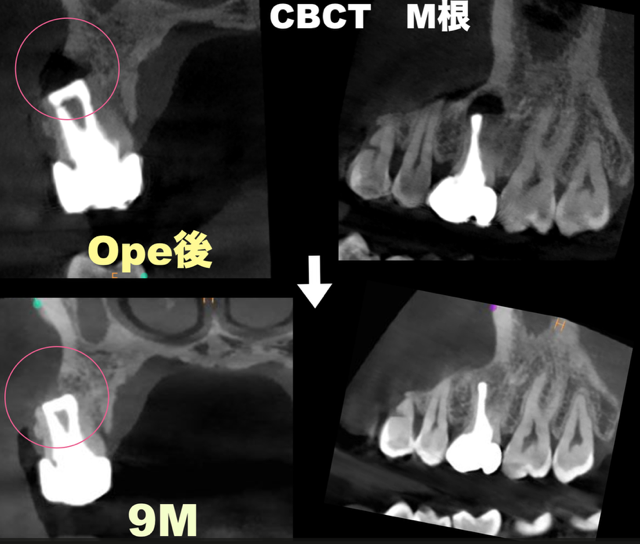

腫れを繰り返した奥歯(右上6番)。歯根端切除術で保存した症例。9ヶ月後の経過。

| 診断名 | chronic apical abscess |

| 治療の方法 | 歯根端切除術 |

手術前は、歯の根の先に黒い影があり、骨が溶けている部位が確認できました。

9ヶ月後にはその部分が白くなり、骨が再生していることが分かります。

黒い部分は骨が溶けていた部位、

白くなった部分は骨が再生した部位です。

このように、歯根端切除術により抜歯と言われた歯でも保存できる可能性があります。